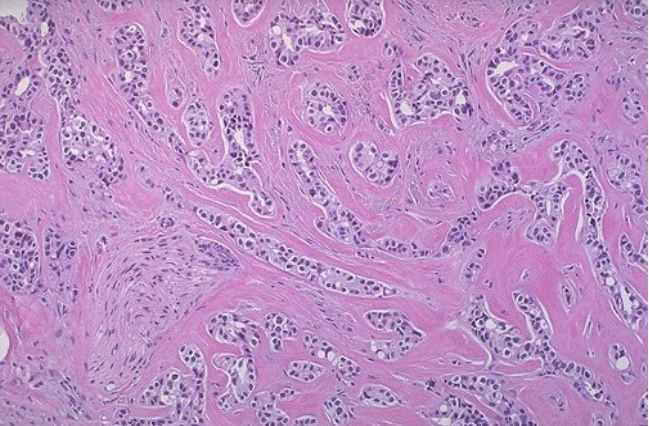

患者,女,35岁,发现右侧乳腺包块2个月,右侧腋窝淋巴结增大2天。肿块质地较硬,边界不清。活检组织学检查图像如图1所示。图2是高倍镜下的一个视野。患者有乳腺癌家族史。

问题3、根据图1的组织学结构,请解释为什么肿瘤比较硬?

图1:右侧乳腺包块活检组织学